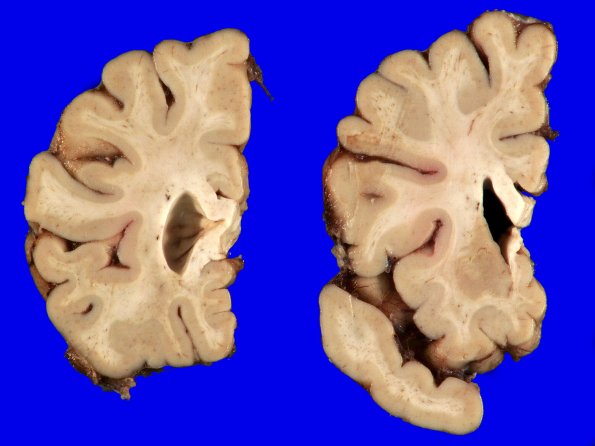

Washington University Experience | NEURODEGENERATION | Huntington Disease | 18A2 (Case 18) Gross _19

There is mild atrophy of the caudate and putamen of the basal ganglia. The ventricular system shows some dilatation with blunting of the angle of the anterior horn of the lateral ventricle.